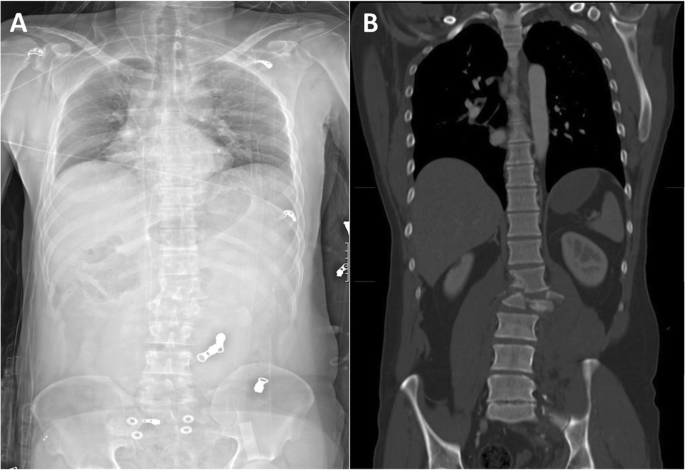

Examples of a misdiagnosed and correctly identified injury are shown in Figs. 3 and 4.

Example of a correctly identified unstable injury using anterior-posterior Lodox Statscan (AP-LS). C-type injury of the 12th thoracic and first lumbar vertebra shown in AP-LS (a) and the corresponding full-body CT scan (b) of 36-year-old men after a car accident. This injury was correctly identified by two of the three observers (Radiologist and Orthopedic attending)